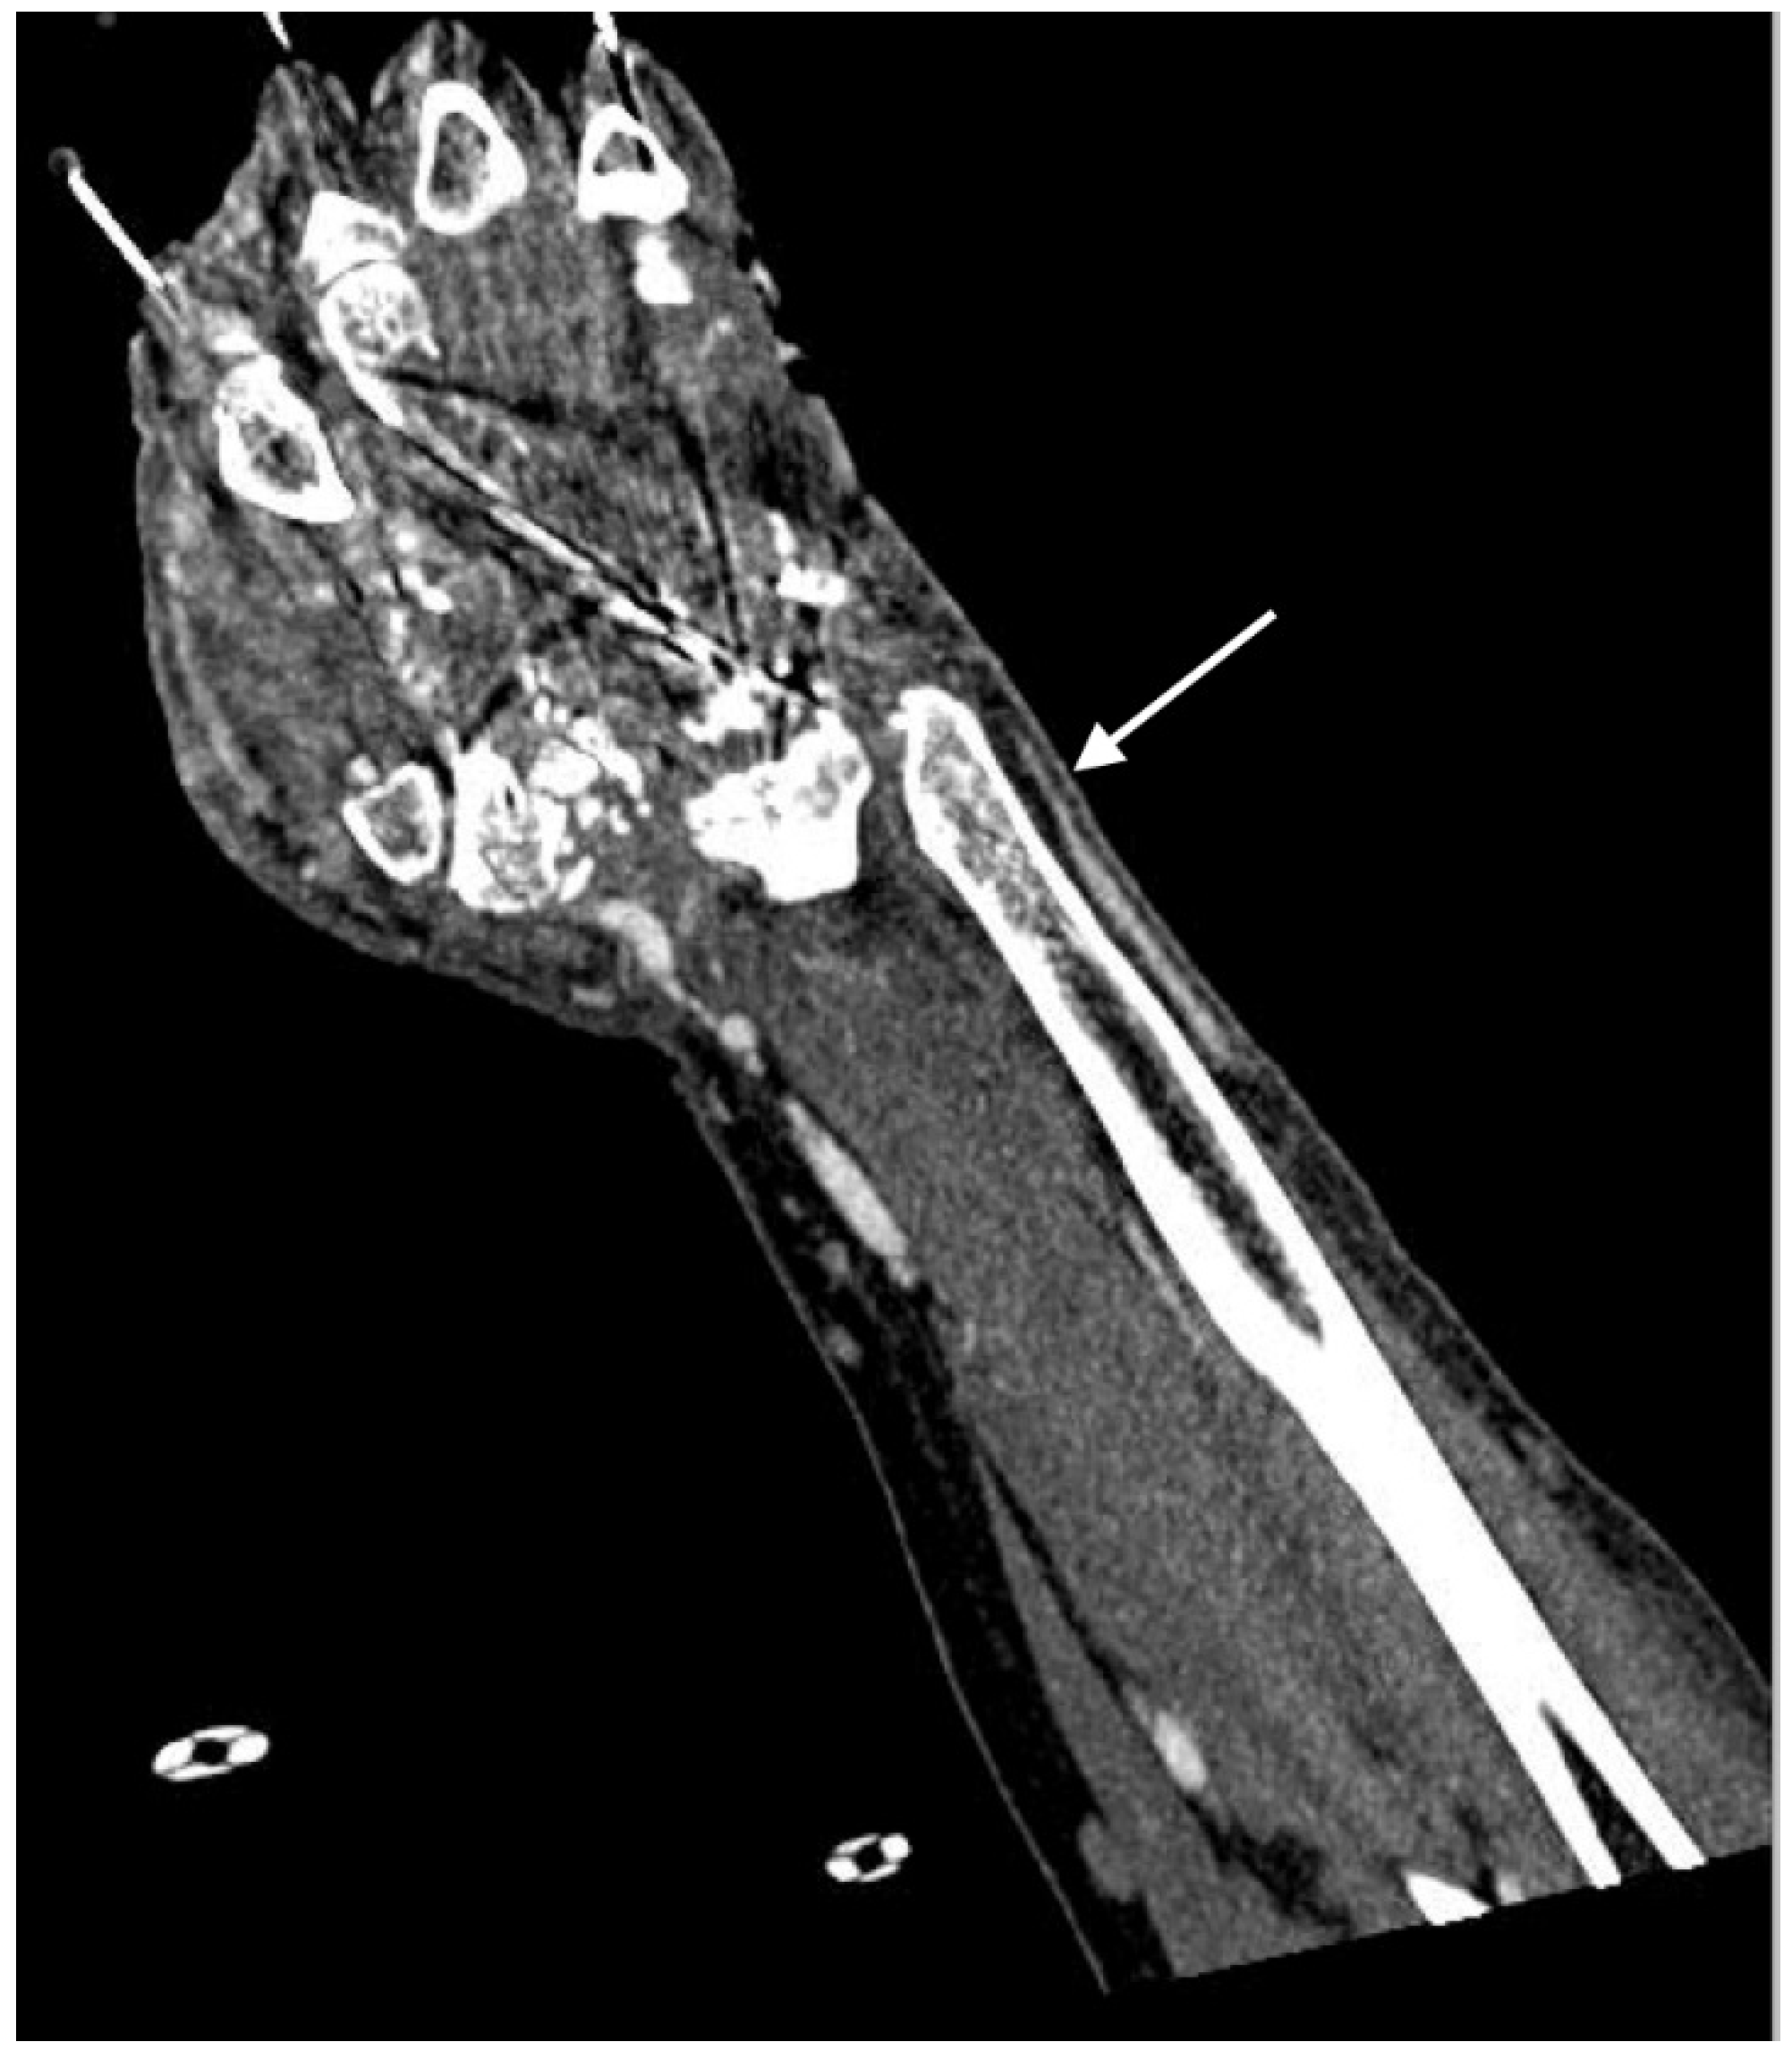

2.4.6. Arteriovenous Fistula